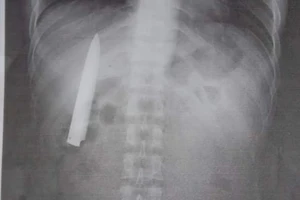

Lưỡi dao kẹt trong ngực gần năm trời mà không hay biết

Cứu sống ngoạn mục người đàn ông bị dao đâm xuyên ngực

Bị dao đâm xuyên não 6 cm vì trượt chân té khi cạo vôi

Cứu sống ngoạn mục thanh niên 18 tuổi bị dao đâm xuyên tim

Cứu sống bệnh nhân suýt tử vong do dao đâm thủng gan

Bị đâm 5 nhát, thủng phổi ngay trong sân nhà

Say rượu, tự dùng dao đâm thủng gan